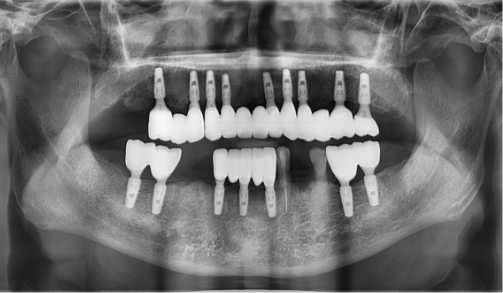

단 하나의 임플란트라도 평생을 함께할 소중한 치아.

목포미르치과병원은 늘 환자의 건강과 만족을 최우선으로 생각합니다.

처음 상담부터 수술, 그리고 회복과 관리까지 1:1 주치의가 전 과정을 함께합니다. 믿을 수 있는 정품 재료와 진심 어린 사후관리로 시간이 지나도 변하지 않는 신뢰를 드립니다.

1:1 주치의 진료 시스템

미르치과는 임플란트 수술부터 관리까지 1:1 주치의 진료 시스템을 통해 평생 동안 관리해 드립니다.